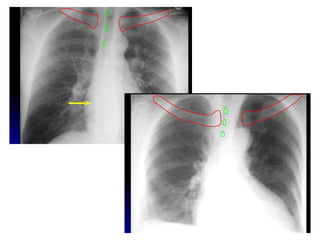

Silhouette Sign

• An intrathoracic lesion touching a border of

the heart, aorta, or diaphragm will obliterate

that border on the radiograph.

• An intrathoracic lesion not anatomically

continous with a border of one of these

structures will not obliterate that border.

• Eg. Lower lobe pneumonia, disease of lingula

Silhouette sign: If the airspace adjacent to one

of the normal mediastinal or diaphragmatic

contours is filled with dense material i.e.

consolidated, then the normal air-soft tissue

interface is lost and the normally seen edge of

the silhouette disappears